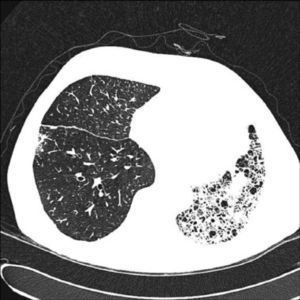

In unilateral transplant recipients, pulmonary function stabilises earlier, around the third month, because there is less trauma from the surgery. In these patients, maximum pulmonary function is lower than in bilateral transplant recipients and is also affected by the characteristics of the residual native lung. In recipients with interstitial disease, there is a tendency for the native lung to collapse, so the graft lung expands freely into the corresponding hemithorax (Fig. 1). There may be mild or moderate residual restriction and altered diffusion due to the presence of the native lung.8

When the underlying disease is emphysema, the residual native lung tends to distend and herniate into the contralateral hemithorax, causing partial collapse of the graft (Fig. 2). Progressive air trapping produces hyperinflation in the native lung, but this does not usually present problems when the lung is functioning adequately. On occasions, the progressive distention of an emphysematous lung may compromise graft function, so volume-reducing surgery on the native lung may be necessary. Interference from an emphysematous lung may mean that functional improvement in these recipients is poorer than in those with interstitial disease. Improvement is also seen in pulmonary volumes, DLCO, gas exchange and exercise capacity.9